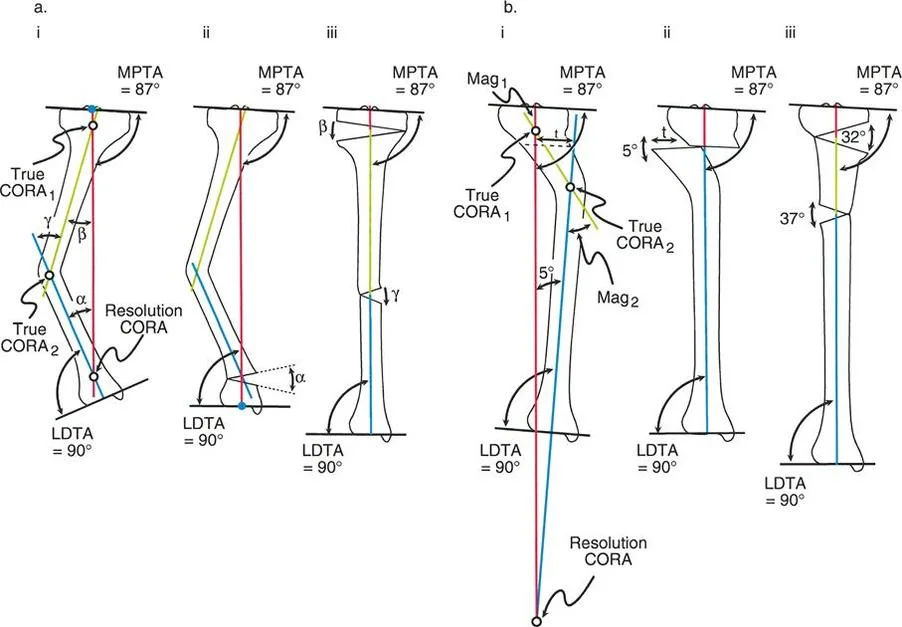

مركز دوران الانحراف (CORA)

يعتبر CORA خاصية أساسية للتشوه في العظم. يُعرّف بأنه نقطة تقاطع خط المحور الميكانيكي (أو التشريحي) القريب وخط المحور الميكانيكي (أو التشريحي) البعيد.

* CORA الحقيقي: هو القمة التشريحية الفعلية للتشوه.

* CORA الحل (Resolution CORA): نقطة نظرية تُستخدم في التشوهات متعددة المستويات حيث تتقاطع المحاور القريبة والبعيدة النهائية، وقد لا تقع هذه النقطة داخل العظم نفسه.

محور تصحيح الزاوية (ACA)

بينما يعتبر CORA حقيقة تشريحية ثابتة، فإن ACA يقع جزئيًا تحت سيطرة الجراح. يمثل ACA النقطة المحورية التي يدور حولها الجزء البعيد من العظم لتحقيق التصحيح.

* الموضع الأمثل: يجب أن يكون ACA موجهًا بشكل عمودي على مستوى التشوه ويمر مباشرة عبر CORA.

مستوى قطع العظم (Osteotomy Level)

مستوى قطع العظم (الشق الجراحي) يقع بالكامل تحت سيطرة الجراح. تحدد العلاقة الهندسية بين مستوى قطع العظم، وACA، وCORA النوع الدقيق للتصحيح الناتج، وتحدد ما إذا كان سيحدث تشوه ثانوي غير مقصود (مثل الانزياح غير المرغوب فيه).

إن فهم العلاقة المكانية بين القطع، والمفصلة، وقمة التشوه هو سر التصحيح الخالي من العيوب. تحدد قواعد بالي لقطع العظم النتائج الميكانيكية لخطتك الجراحية:

القاعدة الذهبية الأولى: القطع والمفصلة عند مركز الانحراف

عندما يمر كل من قطع العظم وACA مباشرة عبر CORA، يتم تصحيح التشوه الزاوي بشكل مثالي. يتم استعادة المحور الميكانيكي، ولا يوجد انحراف في المحور الميكانيكي (MAD)، وتبقى أجزاء العظم القريبة والبعيدة متوازية تمامًا. هذا هو السيناريو المثالي، والذي غالبًا ما يتحقق بقطع عظم وتدي بسيط (فتح أو إغلاق) عند قمة التشوه.

القاعدة الذهبية الثانية: المفصلة عند مركز الانحراف والقطع بمستوى مختلف

في بعض الأحيان، قد يكون قطع العظم مباشرة عند CORA غير ممكن سريريًا بسبب سوء حالة الجلد، أو وجود أدوات جراحية سابقة، أو مشاكل في جودة العظم في منطقة الكردوس/الجذع. إذا بقي ACA عند CORA، ولكن تم إجراء قطع العظم عند مستوى مختلف (أقرب أو أبعد عن CORA)، فسيتم تصحيح التشوه الزاوي بالكامل. ومع ذلك، ستنزاح نهايات العظم عند موقع قطع العظم بالنسبة لبعضها البعض.

* النتيجة السريرية: يؤدي هذا إلى "نتوء" أو تعرج في المحور التشريحي، لكن المحور الميكانيكي العام وتوجيه المفصل يظلان متوائمين تمامًا.